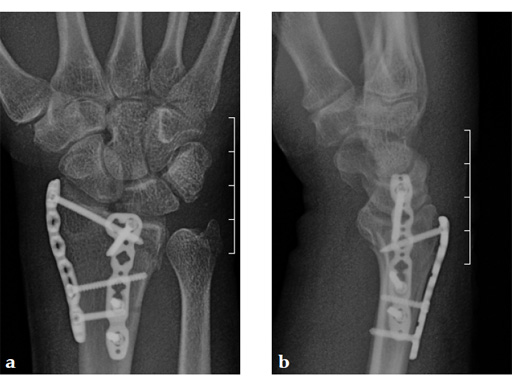

Case 1: A 62-year-old man fell on his outstretched left hand while playing tennis, sustaining an intraarticular fracture of the distal radius, Mller AO Classification 23-C3.2.

Case provided by Renato Fricker, Bruderholz, Switzerland